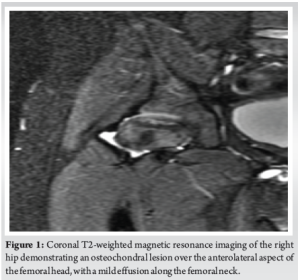

An 8-year-old Hispanic male with no significant medical history presented with bilateral hip pain of eight out of ten on the visual analog scale. He had been followed at a pediatric orthopedic clinic for nearly a year for magnetic resonance imaging (MRI) findings suggestive of bilateral LCP disease at the early fragmentation stage. Lesions were somewhat symmetrical, so a rule out of Meyer’s dysplasia and genetic counseling was done accordingly. Imaging showed 10–15% non-enhancement in the left hip and 10% in the right hip, with more severe avascular necrosis on the right. Scant effusions were noted, without signs of arthrosis or collapse. Given his age and benign diffusion-weighted MRI findings, he was managed conservatively with non-steroidal anti-inflammatory drugs, activity modification, and rest for over a year. Due to persistent pain and unchanged imaging findings, he was referred to our Hip Preservation Clinic. On examination, a functional waddling gait was noted. Bilateral hip flexion was 0–100°, with pain on pure flexion. Internal rotation with flexed hips measured 15° with pain, and external rotation was 40° bilaterally. Anterior impingement and apprehension tests were positive bilaterally. A mucopolysaccharidosis and Sickle Cell panel was ordered and returned negative. Given the benign clinical picture, conservative management continued, including close observation and a 2-month course of physical therapy. At a 4-month follow-up, the patient reported no improvement in pain, and his physical exam remained unchanged. Repeat MRI revealed an under-covered femoral head with a chondral defect partially covered by functional cartilage (Kerboul Grade II) (Fig. 1). A full radiographic workup showed findings consistent with borderline hip dysplasia (Fig. 2), prompting the recommendation for bilateral triple pelvic osteotomies (PAO).